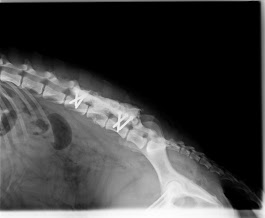

La radiologia è uno strumento diagnostico fondamentale che ci permette di osservare in modo non invasivo l’interno del corpo di cani e gatti, aiutandoci a individuare rapidamente eventuali problemi ossei, articolari, toracici o addominali.

Presso la nostra clinica disponiamo di apparecchiature radiografiche digitali di ultima generazione, che garantiscono immagini ad alta definizione e una riduzione significativa delle dosi di radiazioni. Questo ci consente di ottenere diagnosi precise in tempi brevi e con il massimo comfort per il paziente.